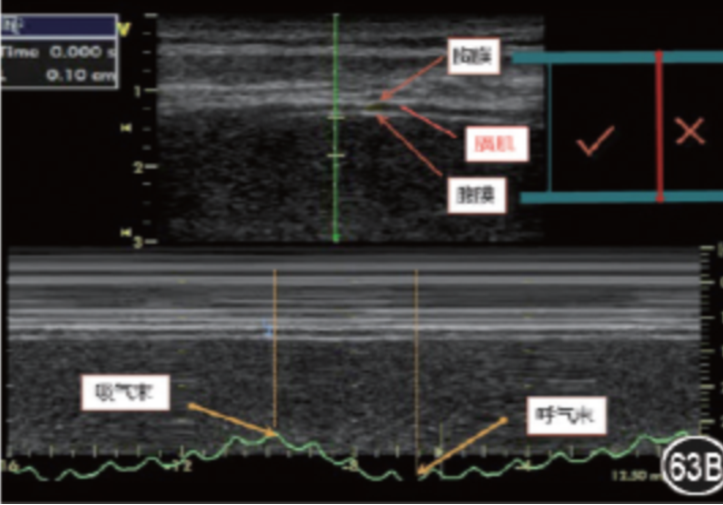

图17为肺超(低频凸阵探头),经腋中线做垂直肋骨的M型超声下可见“肺搏动征”。

图片

图18为膈肌超声,锁骨中线与肋缘的交界处(凸阵低频探头),探头标志朝向外侧,M超模式下观察膈肌运动幅度。